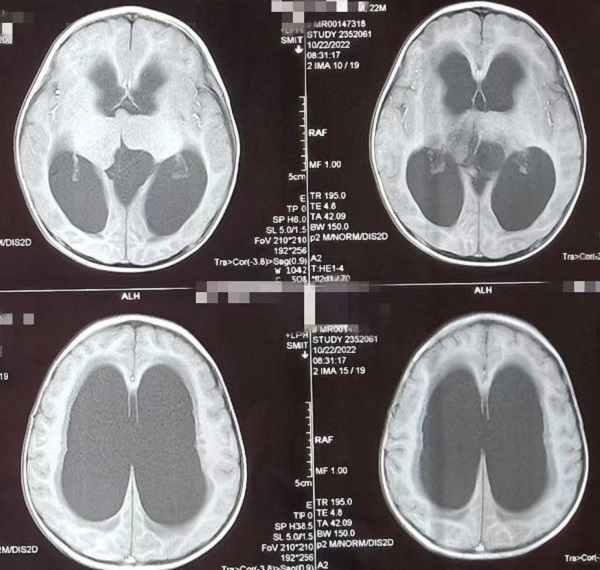

随着神经内镜设备的不断更新和微侵袭技术的快速发展,脑室镜下第三脑室底造瘘术(Endoscopic Third Ventriculostomy,ETV)优势凸显,近日,陕西省核工业二一五医院神经重症监护室在原有内镜技术上再上新台阶,突破“...